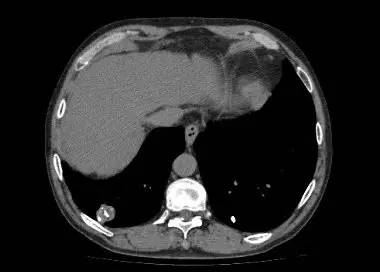

男,52岁,查体发现肺部病变

[影像描述]

右肺下叶结节样病变,内有钙化、脂肪成分,增强后可见轻度强化。

[检查结果]

右肺下叶错构瘤.

右肺下叶病变内有钙化、脂肪成分,典型爆米花样钙化,增强后可见轻度强化。